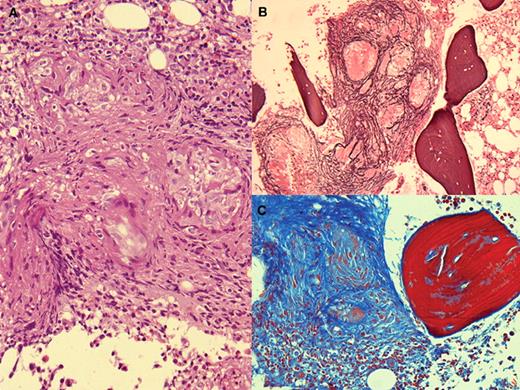

A 44-year-old woman was evaluated for a 2-month history of asthenia, weight loss, and nightly fever. She had no hepatosplenomegaly or adenopathy. The complete blood count and the basic chemistries were normal as were the radiologic examinations of the chest and abdomen. Cultures of blood and urine and serologic studies for rickettsia, chlamydia, brucella, Legionella, and Mycoplasma were negative. Sputum for Mycobacteria was negative. Bone marrow aspirate showed no abnormalities of marrow elements but noncaseating granulomata were observed in the H&E stain of the biopsy (panel A). In addition, the silver nitrate stain (panel B) and Masson trichrome (panel C) showed fibrosis. The acid-fast stain and marrow cultures were negative. Angiotensin-1 converting enzyme was shown to be elevated (119 UI/L).

A diagnosis of sarcoidosis was suggested based on the marrow, clinical findings, and the elevation of angiotensin-1 converting enzyme. Adalimumab was initiated and the patient improved with the disappearance of constitutional symptoms and fever. A follow-up bone marrow has not yet been performed.

Bone marrow granulomata are often found without well-defined causes. Sarcoid granulomata are infrequent, perhaps related to the fact that bone marrow studies are not routine investigation for sarcoidosis.